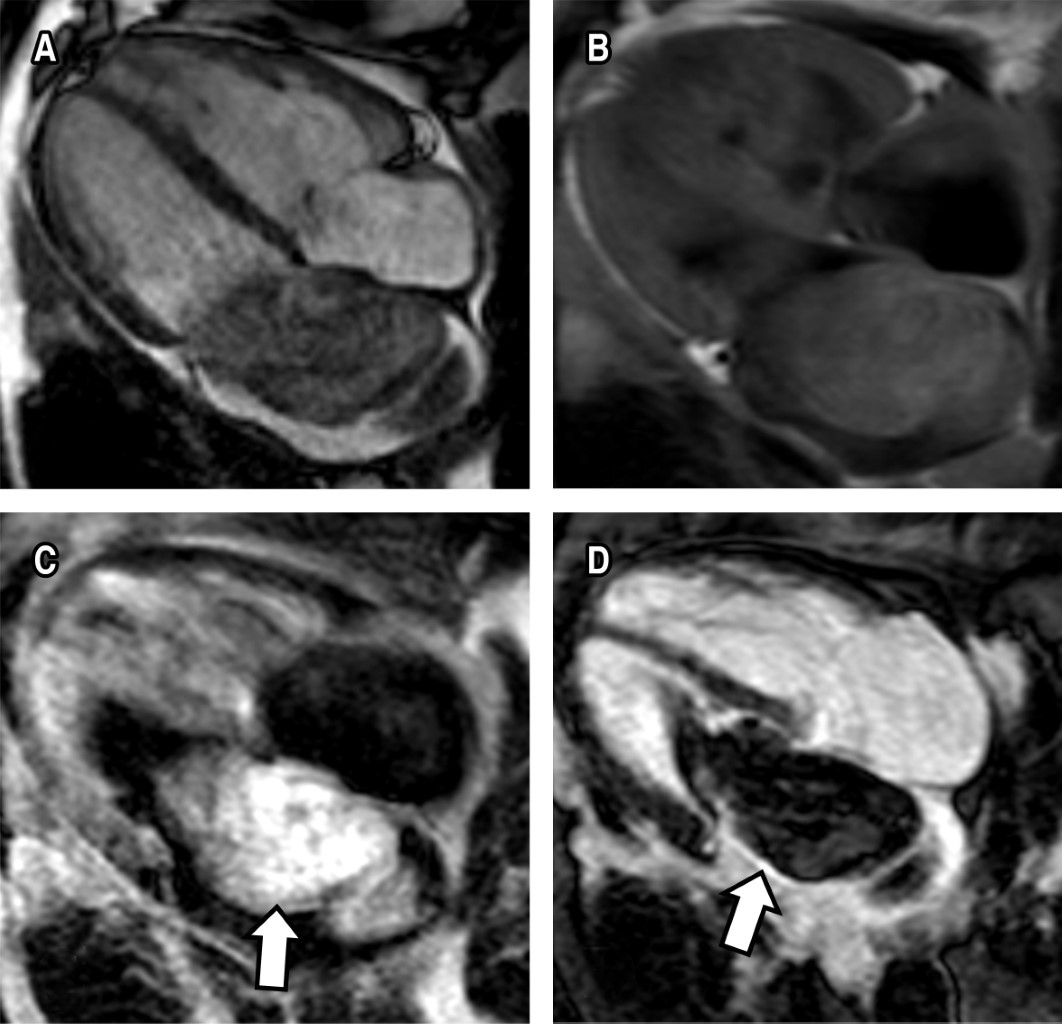

Mixoma Cardiaco